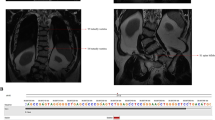

The outcomes of all pregnancies are summarized in Table 1, Figs. 1 and 3, where we categorize them according to the Nosology 2023 [1]. Radiographs of nine fetuses are provided in Fig. 2. Radiographs of fetus numbers 12 and 21 have already been published [8, 21]. For case 28, the radiographs were obtained postnatally (Fig. 4).

CT at 3 years and radiographs at 1 month of age. A Cerebral CT, showing molar tooth sign (arrow). B Chest, thoracic cage is within normal range. C Lateral spine, with normal height of vertebral bodies. Note sporadic coronal clefts (arrow). D Right upper extremity, normal. E Lower right extremity shows short tibia and broad diaphyses. Proximal tibial epiphysis is not ossified. F Pelvis, normal. Note short femoral necks (arrows). G Right hand with a rudimental postaxial extra finger (arrow). H Foot, note preaxial polydactyly (arrow).